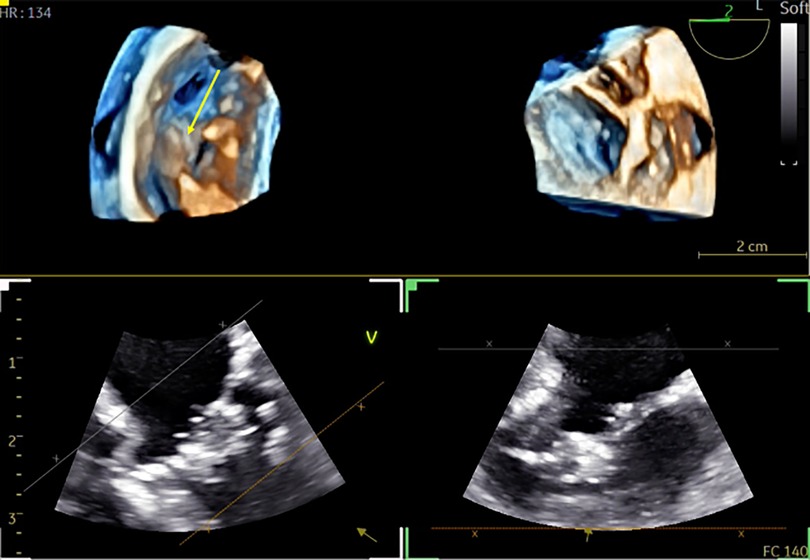

FIGURE 10

www.frontiersin.org

Figure 10. 3D TOE in a 5.8 kg patient with repaired intermediate atrioventricular septal defect. Dual cropping views on 3D real-time of the left atrioventricular valve with the cleft closure (yellow arrow) from the LV (left panel) (Supplementary Video S13). 3D, three-dimensional; LV, left ventricle.

Clinical impact in 14 examinations (out of 60): In two patients, reintervention was needed due to severe residual regurgitation of the left atrioventricular valve, as visualized on TOE. Additionally, in one patient, the diagnosis was corrected from mitral valve stenosis to supravalvular membrane, thanks to the enhanced visualization provided by 3D images (Figure 6 and Supplementary Video S9). Six patients underwent percutaneous closure of ostium secundum atrial septal defect (ASD). The 3D provides an en-face view of the ASD with a comprehensive view of the surrounding edges at a single glance (Figure 7 and Supplementary Video S10). In 2 patients, the ventricle septal defect (VSD) was better delineated with 3D, having a slit-like shape, allowing for a more appropriate choice of the percutaneous prosthesis (Figure 8 and Supplementary Video S11). One subaortic membranous was better defined by 3D having a semi-circular shape which helps the surgeon (Figure 9 and Supplementary Video S12). In 2 cases TOE improves postoperative understanding: (1) After cleft closure in intermediate atrioventricular septal defect the 3D image displayed very well the sutured cleft which is not visible in 2D images (Figure 10 and Supplementary Video S13); (2) After a modified Konno (to release the obstruction in hypertrophic cardiomyopathy) the muscular septal resection with the interventricular septum patch and its relationship with the anterior mitral valve was clearly defined by 3D images (Figure 11 and Supplementary Video S14).